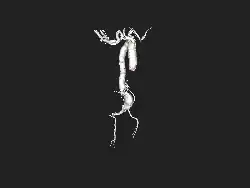

| Angiography of an aneurysm in a brain artery. The aneurysm is the large bulge in the center of the image. | |